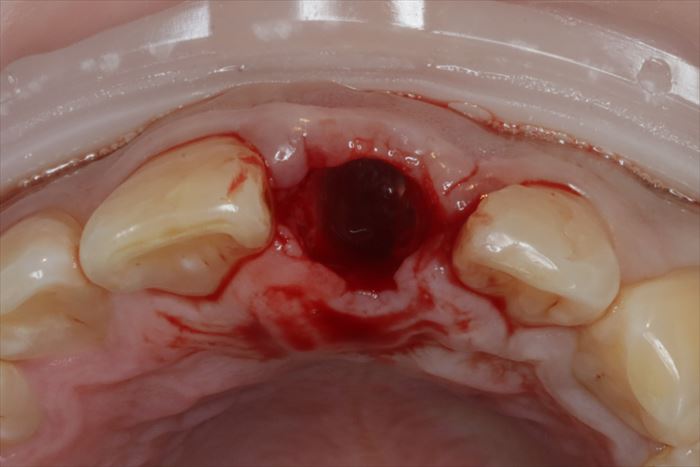

抜歯後の状態です。

ここからドリリングしてインプラントを埋入する穴=インプラント床(しょう)を形成します。